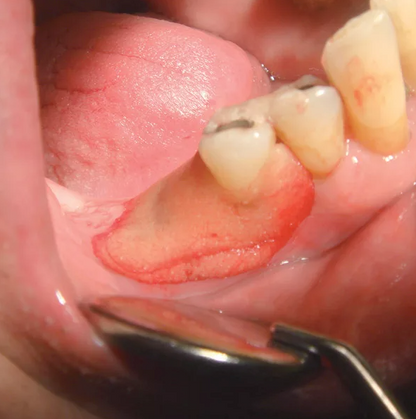

Reso-Pac is easily and perfectly formed to the wound area and adheres up to 30 hours – even on damp and bleeding wounds (slowly dissolves).

No Taste – No Odor – No Mixing

Self Absorbing

Biocompatible